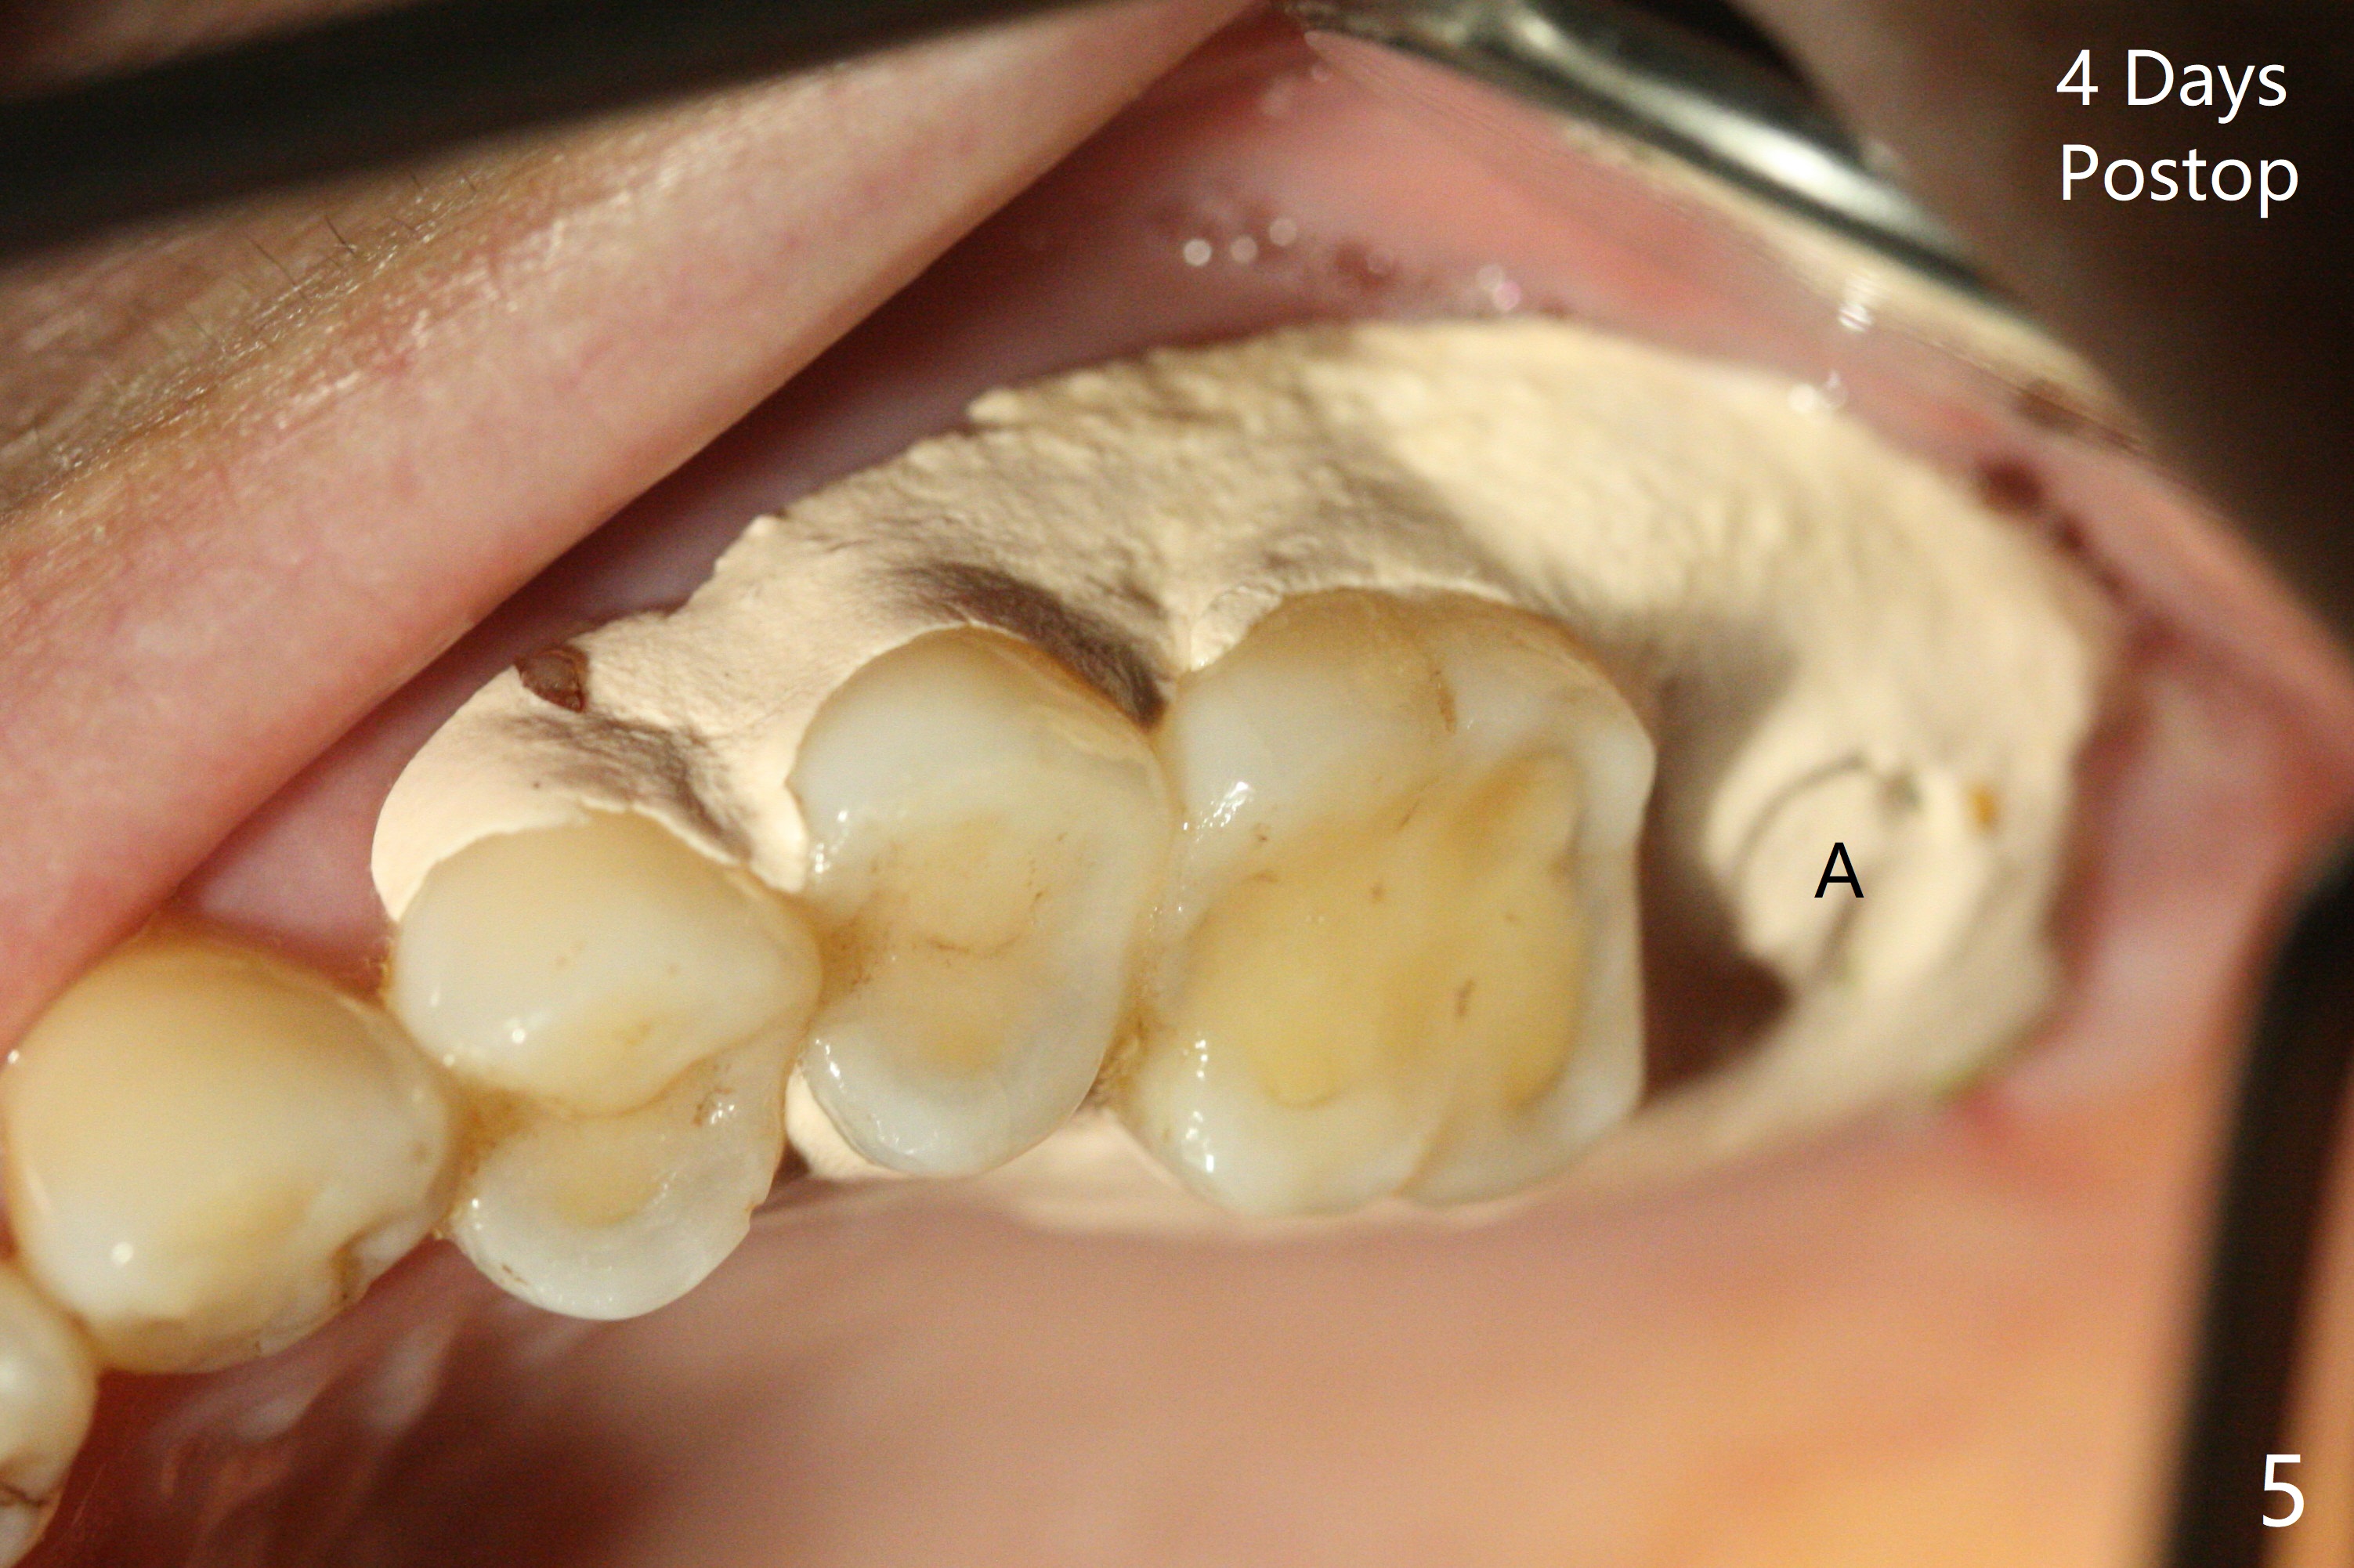

A 56-year-old woman has sign of periimplantitis 2 years 9 months post cementation. After incision, the 5.5x13 mm bone-level implant is ~ 3 mm inferior to the buccal crest. The implant is removed with 7/6 mm trephine bur, elevator and implant driver. The sinus membrane perforates. A 8x17 mm tap achieves stability (Fig.1), but the peripheral bone seems to be thin. Although a 7x14 mm tissue-level implant has stability, it is placed too deep (Fig.2). Following insertion of a piece of Osteogen plug for sinus membrane repair, a 8x14 mm implant is placed with >40 Ncm with allograft placed around the unpolished portion of the implant (Fig.3,4). A 6x3 mm abutment is placed to hold periodontal dressing in place. Because of the abutment with a slot (Fig.5 A), the periodontal dressing remains in place 4 days postop before the patient travels back home for 4 hours. In fact there is no postop sinus infection; the implant threads seems not be exposed 3 months postop (Fig.6). Because of the large implant, it is loaded early (Fig.7, 8 (Temp Bond)). Upper Molar Immediate Implant, Trajectory II 劈开术 Xin Wei, DDS, PhD, MS 1st edition 08/09/2019, last revision 04/11/2021